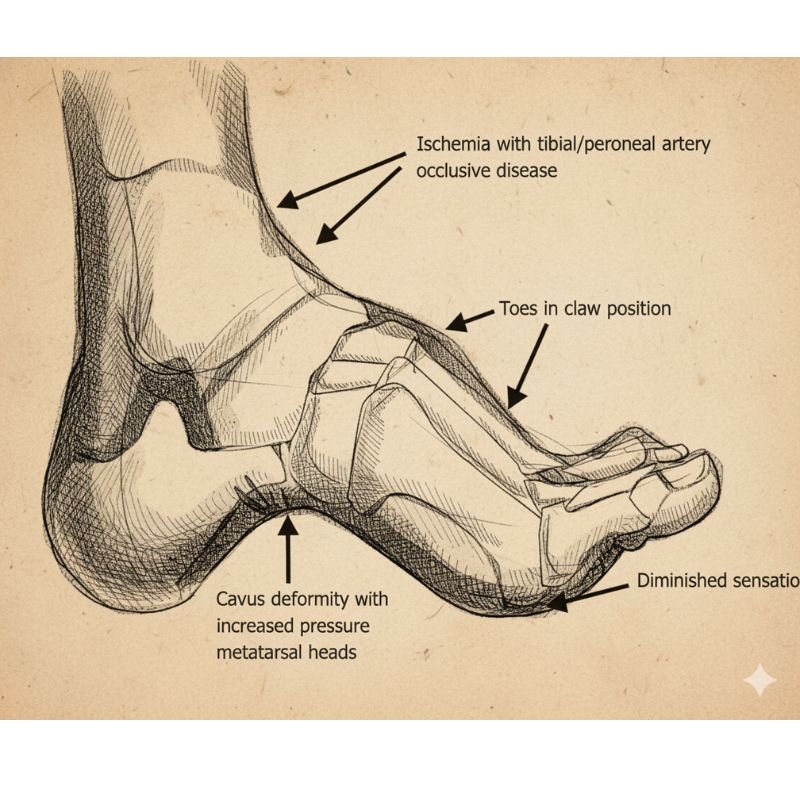

Diabetic foot refers to a range of foot problems that develop in people with long-term high blood sugar levels. Over time, diabetes damages small blood vessels, reducing blood flow to the feet.

It also causes nerve damage or peripheral neuropathy, which lowers sensation and makes it harder to feel pain, pressure, or injuries. As a result, even minor cuts & wounds go unnoticed.

Poor circulation and high blood sugar create an environment prone to infections and impaired healing. If left untreated, these injuries can turn into non-healing ulcers and, in severe cases, lead to gangrene (black foot), where tissue dies and amputation may be necessary.

Diabetic foot problems often develop gradually due to glycation, where high blood sugar binds with fats & proteins in the bloodstream to form advanced glycation end-products (AGEs).